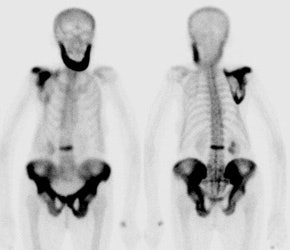

Pagets disease affects between 3% to 4% of the population over the age of 40 years and up to 10-11% after age 80 years [1]. Although the actual cause of Pagets disease is not known, a viral etiology has been postulated due to the presence of intra-nuclear inclusion bodies which resemble viral nucleocapsids within the osteoclasts of Pagetoid bones [1]. The most commonly involved bones are the vertebral bodies (30-75%), skull (25-65%), pelvis (30-75%), and proximal long bones (25-30%) [1]. Monostotic disease occurs in 10-35% of cases and is more often seen in the axial skeleton [1]. Polyostotic disease (65-90%) occurs more commonly [1]. Symptoms include pain, bowing deformities, kyphosis of the spine, and bone enlargement [1]. About 20% of affected patients are initially asymptomatic [1].

There are generally considered to be 3 phases to the disorder- lytic phase, mixed phase, and blastic phase. Initially, intense osteoclastic activity produces the lytic or incipient active phase. Lytic findings are more commonly seen in the skull and long bones. In the skull, involvement is refered to as osteoporosis circumscripta which produces well defined areas of lucency in the occipital and frontal bones [1]. The is notable absence of peripheral sclerosis surrounding the lucent areas [1]. Both the inner and outer calvarial tables are involved [1]. In the long bones, the process begins in the subchondral area of the epiphysis and extends along the shaft in a characteristic wedge-shaped ("flame" or "blade of grass") appearance. The lytic phase is followed by the mixed or fibrous phase in which bone marrow is replaced by very vascular fibrous tissue. There is coarsened thickening of the trabecular pattern and cortex [1]. In the vertebral bodies, osteoblastic activity is seen along all 4 margins producing a "picture frame" appearance [1]. There is also "squaring" of the normal concavity of the anterior margin of the vertebral body [1]. Disorganized ossification and deformities or fractures may occur. Finally, the disorder become quiescent with the involved bone generally appearing enlarged and sclerotic.

During the lytic portion of the disease lesions may demonstrate uniform increased tracer accumulation, or may have relative photopenia in their center producing a "donut" appearance. In the long bones, increased tracer activity is particularly prominent along the advancing edge of the disorder. Scintigraphy is more sensitive than plain films for disease detection and extent during the lytic phase.

During the fibrous phase, the bone scan demonstrates marked

increased uptake of tracer

in the involved areas. The bone scan can be used to document the

effectiveness of therapy

in these patients. Later, during the sclerotic phase, the bone

scans will begin to show

less intense tracer accumulation and may become normal.

Pagets Disease: Multiple sites of involvement by Pagets disease including the jaw. |